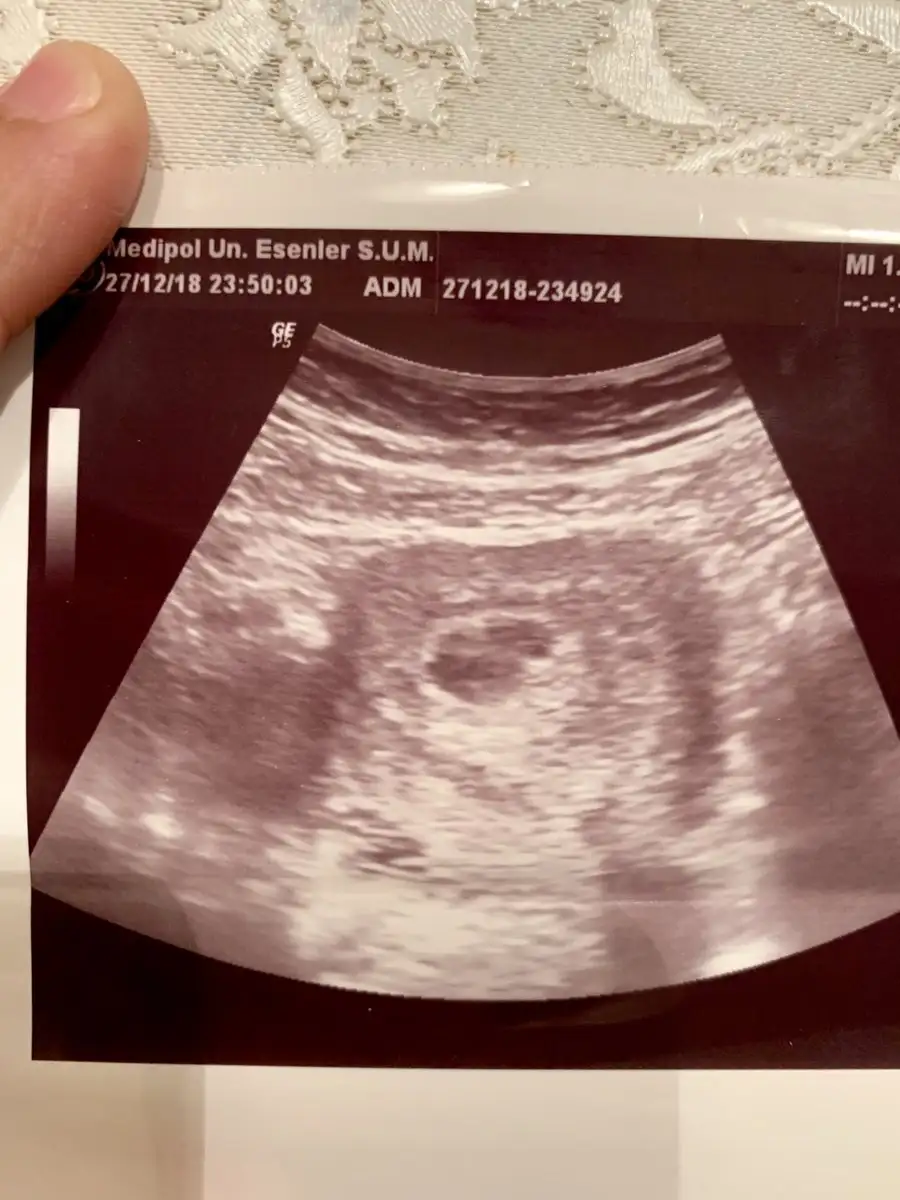

MERHABA KİZLAR DOKTORDAN GELDİM NORMALDE 7+6 BUGUN KALP ATİSİ İCİN GİTTİK DOKTOR İKİZ GEBELİK YADA KAN ODAGİ VAR DEDİ YANİ DUSUK TEHLİKESİ DE OLABİLİR AMA BUYUK İHTİMAL İKİZ DEDİ SİZCE İKİZ Mİ